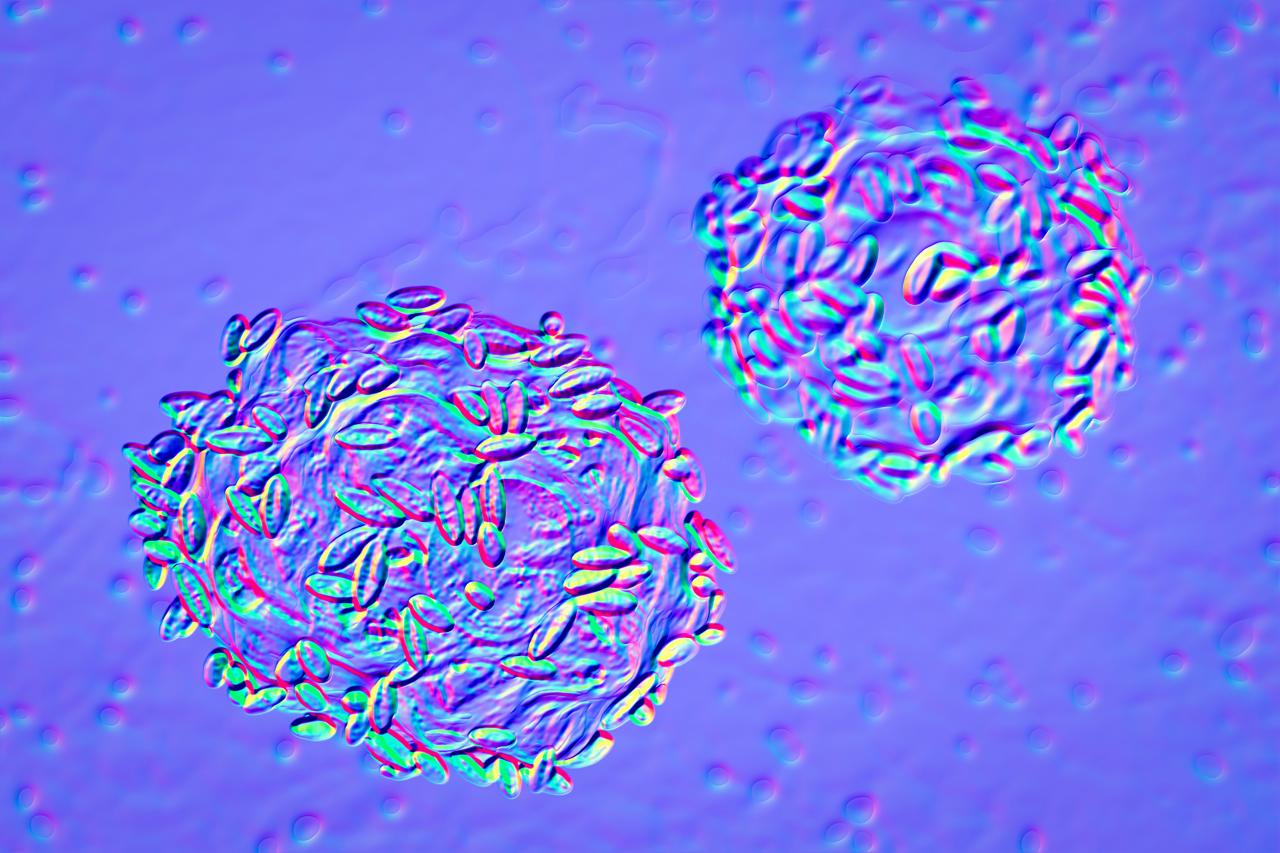

健康的陰道菌群以乳桿菌為主;在這張覆蓋上皮細胞的插圖中,轉移到許多細菌物種的混合體——包括Gardnerella細菌——會導致細菌性陰道病。圖片來源:PNAS

紐約大學格羅斯曼醫(yī)學院(NYU Grossman School of Medicine)生物學家Mykhaylo Usyk解釋說,在放大鏡下觀察,宮頸看起來像一個遙遠的星球。它是圓形光滑的,呈粉紅色,在宮頸中心有一個火山口,它是通向子宮的緊密收縮的門。在這個“遙遠的星球”上,有一個復雜的細菌生態(tài)系統(tǒng),它包括桿狀的乳酸菌屬(Lactobacillus)等物種。健康的陰道菌群以乳酸菌屬為主;而多種細菌混合可能會導致菌群失衡,臨床上稱之為“細菌性陰道病”,或BV(bacterial vaginosis,引起陰道細菌性感染的菌群)的不適癥狀。這種“多微生物狀態(tài)”也增加了感染某些性傳播疾病的風險,比如HPV。

2020年,Usyk與美國紐約阿爾伯特·愛因斯坦醫(yī)學院(Albert Einstein College of Medicine)的科學家Robert D. Burk合作,研究陰道-宮頸菌群的變化如何導致持續(xù)的HPV感染。他們使用了哥斯達黎加一項大型隨機HPV疫苗試驗的縱向數(shù)據(jù)。該試驗包括273名未接種疫苗的HPV感染婦女。Usyk和Burk分析了273名女性的細菌群落,發(fā)現(xiàn)她們的微生物組分為四種不同類型:兩種以乳酸菌屬為主,一種以陰道嗜血桿菌(Gardnerella)為主,還有一種特征是多種細菌物種混合。事實證明,具有陰道嗜血桿菌主導的微生物組的女性,比其他組的女性更有可能出現(xiàn)持續(xù)性HPV感染,導致癌前病變。根據(jù)2020年的研究,某些BV相關細菌也可能加大持續(xù)性HPV感染的風險。